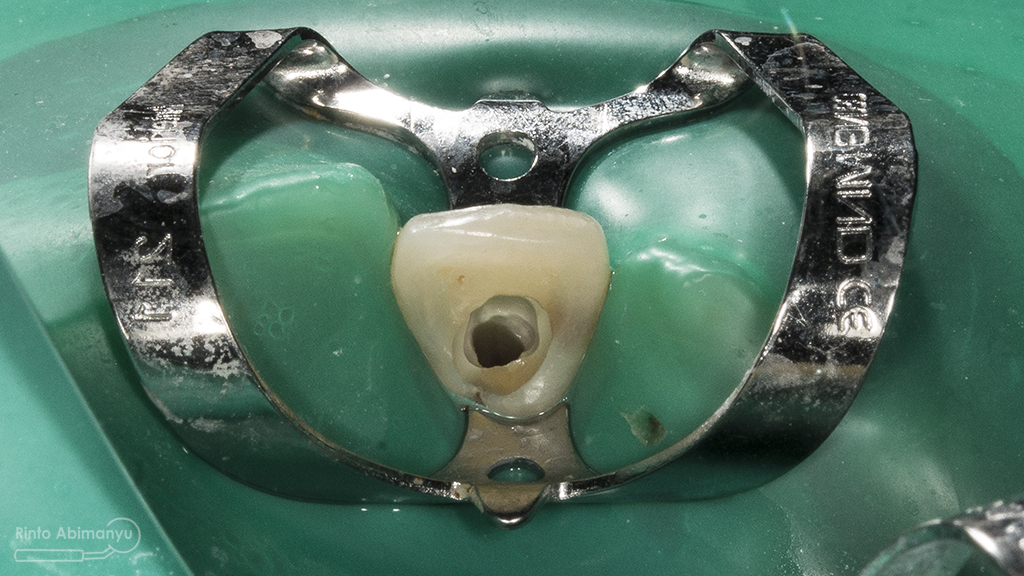

Untuk kunjungan pertama ini saya rencanakan melakukan perawatan saluran akar langsung pada dua gigi central… Saya pasang rubber dam untuk mengisolasi daerah kerja

Gigi 11 21 setelah dipasang rubber dam